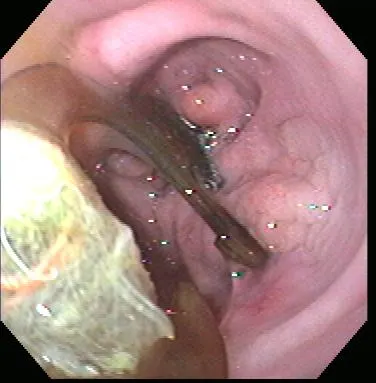

Gastroenteroscopy revealed a hard plastic foreign body (Figure 2) with curved, pointed ends. Points of the object were embedded in the gastric antral mucosa, resulting in hyperplasia. One of the curved points extended through the pylorus and hooked into the proximal duodenum (Figure 3). The endoscope could be passed around the foreign body into the duodenum, allowing biopsy of the duodenal mucosa. The gross appearance of the duodenal mucosa was normal (Figure 4). Attempts to remove the foreign body endoscopically were unsuccessful. Before the dog was sent to surgery for removal of the foreign body, colonoscopy was performed. The colon appeared normal on gross inspection (Figure 5). Biopsies were obtained from the cecum; ascending colon; transverse colon; and proximal, middle, and distal descending colon. At surgery, a gastrotomy incision was made in the pyloric antrum and the foreign body was forcefully removed. It was a plastic object used to secure the legs of a turkey carcass.

Healthy proximal duodenum

Healthy descending colon

In this case, the foreign body could have contributed to the vomiting but may not have been the sole cause (it could have accounted for the apparent progressive course). Gastrointestinal biopsy specimens should always be obtained during endoscopy to investigate the cause of chronic vomiting and/or diarrhea, even if the gastric and intestinal mucosa appear normal.